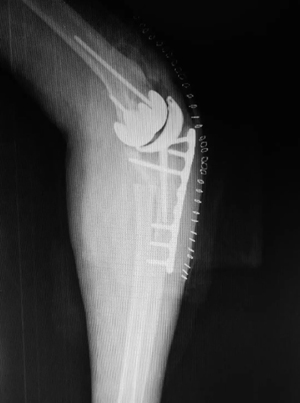

团队联合爱康医疗,以该患者的肘关节CT为基础,历经2个半月的设计和不断改良,考虑了关节稳定性、假体固定和骨长入等相关问题,定制了一套符合临床需求的肘关节表面置换假体(图2),患者也十分配合的耐心等待。4月14日上午八点四十,在麻醉科和手术室的全力配合下,这台手术终于顺利开台。蒋协远教授带领团队经过两个多小时的努力,手术顺利完成,术中患者的屈伸和旋转活动度均恢复至正常水平,并且关节稳定(图3)。目前患者正逐步康复中。

图2 假体和截骨模块的设计和改良。